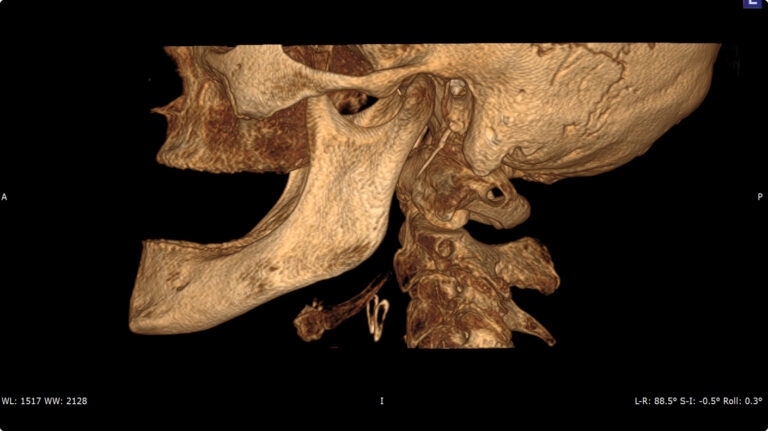

Мультиспиральный томограф выполняет послойное сканирование области верхней и нижней челюстей с помощью рентгеновских лучей, а затем, используя компьютерную обработку данных, создает 3D-модели исследуемой зоны. Современные модели томографов проводят круговое сканирование по спирали, делая срезовые снимки на расстоянии 0,5 мм друг от друга. Затем на основе этих данных реконструируются детальные изображения челюстно-лицевой области в трехмерном формате.

В отличие от конусно-лучевой компьютерной томографии (КЛКТ), которая также в последнее время применяется в стоматологии, МДКТ помогает лучше визуализировать костные структуры на фоне артефактов от имплантов и протезов, выполнить сканирование быстрее, без двигательных артефактов, в любом объеме под запрос вашего ортодонта.

- Широкие возможности диагностики. На трехмерных изображениях можно увидеть в целом верхнюю и нижнюю челюсть, включая гайморовы пазухи, височно-нижнечелюстные суставы. Помимо костной ткани при проведении КТ можно оценить состояние окружающих мягких тканей. Это бывает особенно важно при выборе оптимального способа протезирования и имплантации, при подозрении на опухолевые процессы, при планировании оперативного вмешательства.